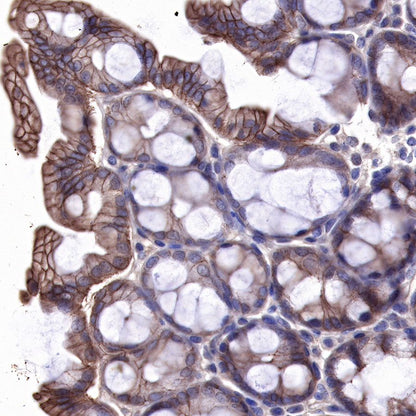

IHC shows positive staining in paraffin-embedded human colon. Anti-EGFR antibody was used at 1/2000 dilution, followed by a HRP Polymer for Mouse & Rabbit IgG (ready to use). Counterstained with hematoxylin. Heat mediated antigen retrieval with Tris/EDTA buffer pH9.0 was performed before commencing with IHC staining protocol.

IHC shows positive staining in paraffin-embedded mouse colon. Anti-EGFR antibody was used at 1/500 dilution, followed by a HRP Polymer for Mouse & Rabbit IgG (ready to use). Counterstained with hematoxylin. Heat mediated antigen retrieval with Tris/EDTA buffer pH9.0 was performed before commencing with IHC staining protocol.